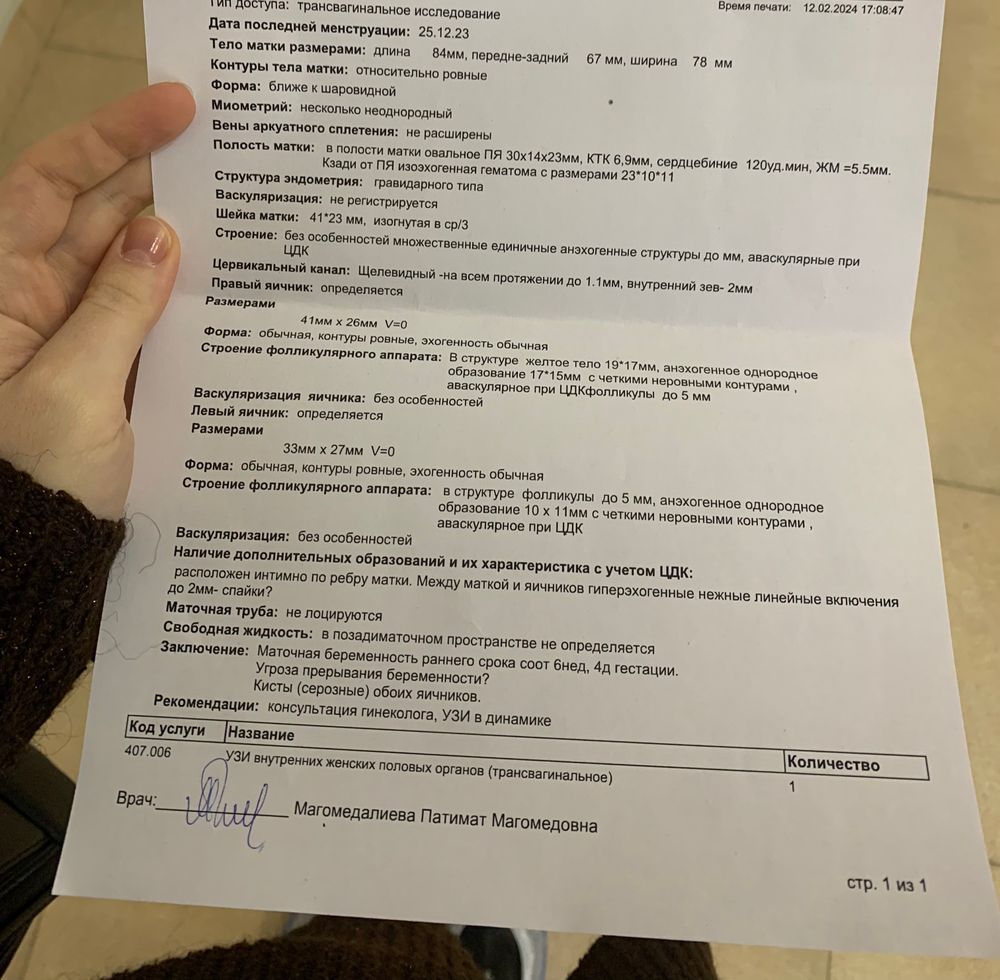

Не знаю, радоваться или нет, но нашли гематому за пя…прописали постельный режим и папаверин. Завтра повторный хгч, в пт снова прием гинеколога и повторное узи. За 4 дня мы хорошо выросли ктр с 2,8 стал 6,9. Но напугали сб всего 120 ударов в минуту… и из-за этой гематомы, она прямо за пя, пя более овальной формы…. Я получила ответы, но теперь еще страшнее… что теперь делать с этой гематомой, сколько она будет выходить, что с сб( 8-го февраля его еще не записывали, слишком маленький был), и пя какой-то формы… давление у меня 90/55 , но сердце стучит ужасно… поделитесь пожалуйста своими историями с гематомами и таким сб… впервые столкнулась